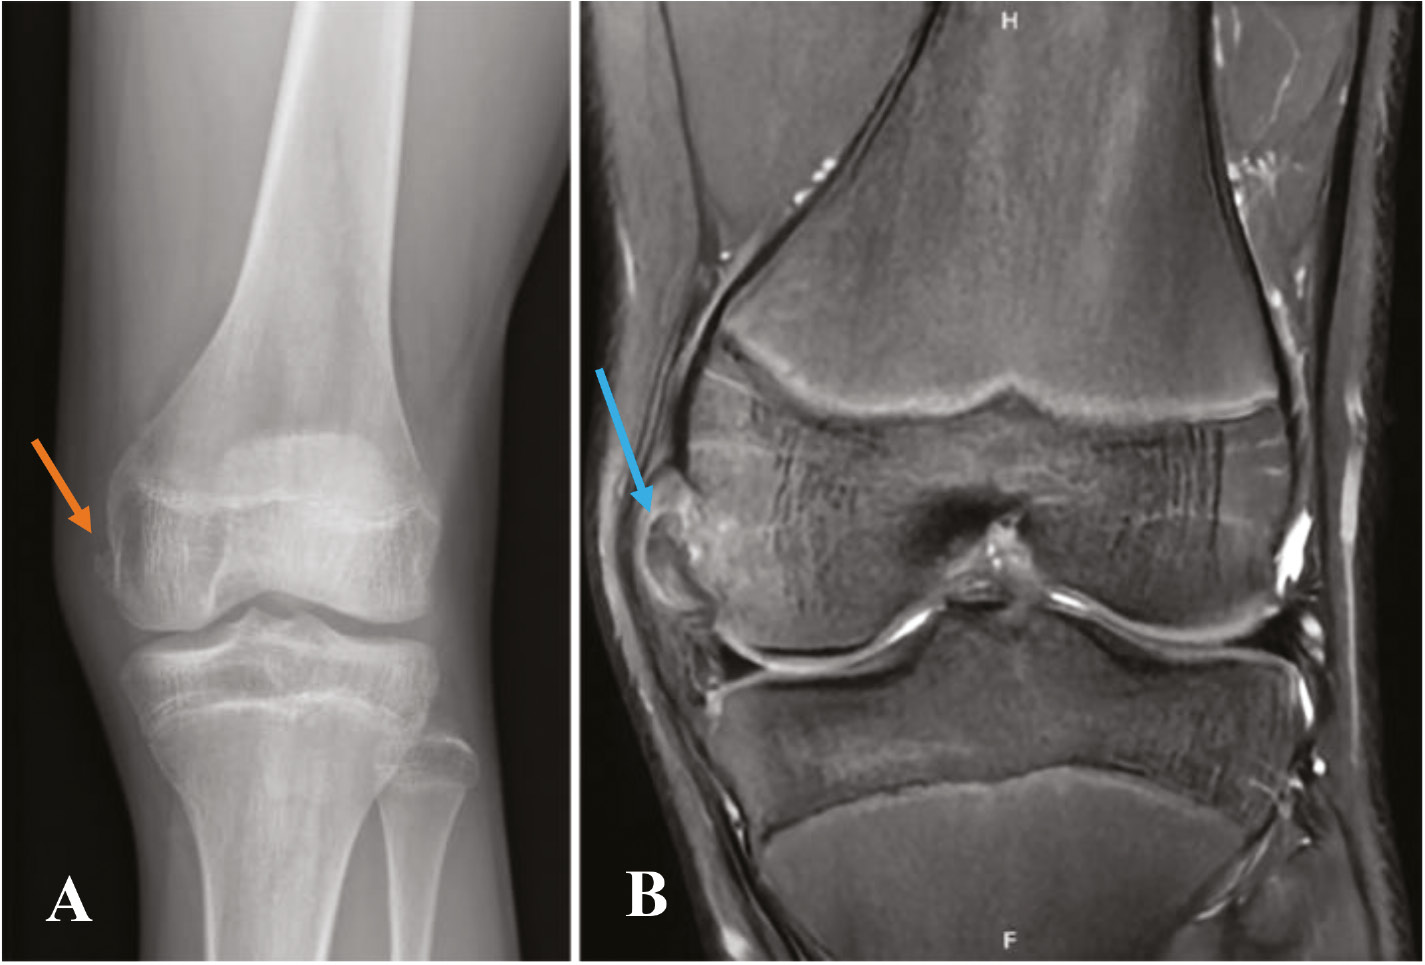

At a minimum, two radiographs (AP/lateral views) of the knee should be obtained, but a four-view series (AP/lateral/merchant/tunnel views) may be preferable to minimize the chance of missing other pathology. Examples would be a Salter-Harris III fracture of the medial femoral condyle, which represents a transitional fracture that is seen in adolescents near skeletal maturity as an alternative to an adult MCL injury (Figure 2). Additional injuries to the MCL complex include medial epicondyle fractures or fractures to the most prominent aspect of the medial condyle, bony avulsions of the deep MCL, which are frequently associated with ACL tears (Figure 3), or even the rare Salter-Harris I or II fracture of the proximal tibia in which the MCL can become interposed within the fracture (Figure 4). With longer-term follow-up, periosteal avulsions of the MCL adjacent to the medial epicondyle may result in the formation of a Pellegrini-Stieda lesion where ossification of the proximal MCL is present from either a previous avulsion of the MCL or ossification within the MCL from a chronic tear/injury pattern (Figure 5). In cases of chronic instability with suspected genu valgum, a long leg alignment film is helpful in quantifying any underlying coronal plane malalignment that may need to be corrected simultaneously or prior to a ligamentous reconstruction.

Figure 3. (A) AP radiograph demonstrating a bony avulsion of the proximal deep MCL (orange arrow). (B) Coronal image better demonstrates the deep MCL avulsion (blue arrow).